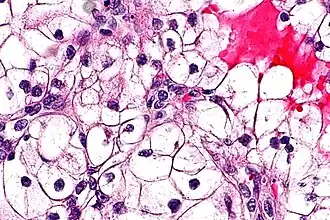

![]() Типичная гистологическая картина светлоклеточного рака почки в высоком разрешении. Окраска гематоксилином и эозином. | |

Клетки светлоклеточного рака почки обычно имеют светлую, прозрачную цитоплазму, хорошо различимую клеточную мембрану, и содержат шарообразное, более или менее обычно выглядящее, ядро[2].

Консенсусом экспертов ВОЗ предложена следующая градация степени злокачественности светлоклеточного рака почки по микроскопически наблюдаемой гистологической картине[2]:

- 1-я степень: Клетки опухоли имеют базофильное и, в целом, не выглядящее сколь-нибудь подозрительным, ядрышко, которое с трудом различимо при увеличении в 400 раз;

- 2-я степень: Клетки опухоли имеют очерченное, хорошо различимое при увеличении в 400 раз ядрышко с эозинофильной, а не с базофильной окраской;

- 3-я степень: Клетки опухоли имеют очерченное и более крупное, чем в первых двух случаях, ядрышко, которое хорошо различимо уже при увеличении не в 400, а всего в 100 раз;

- 4-я степень: Клетки опухоли проявляют высокую или очень высокую (исключительную) степень плеоморфизма (то есть морфологически мало похожи одна на другую, имеют необычно большие различия строения и внешнего вида), выглядят низкодифференцированными, или же имеют рабдоидную либо саркоидную морфологию.